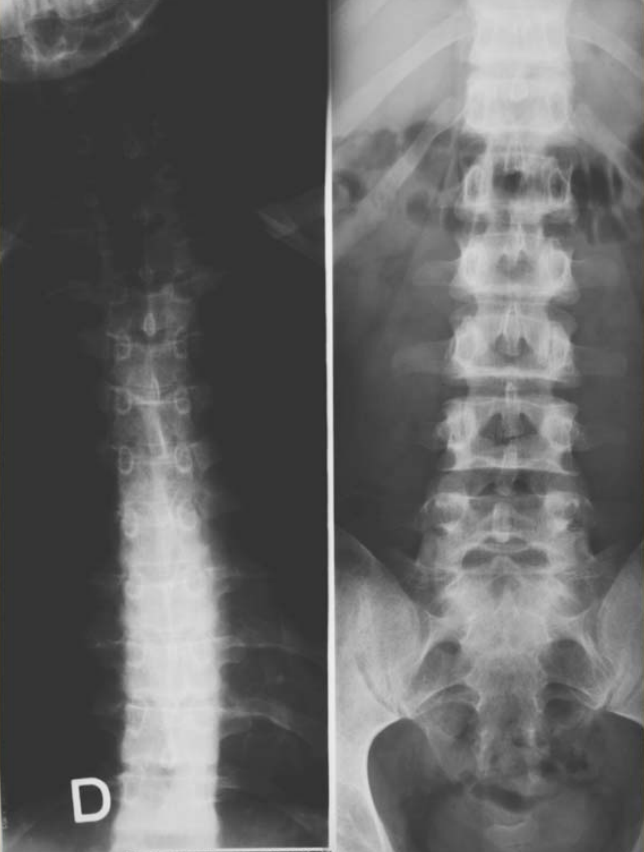

Figure1